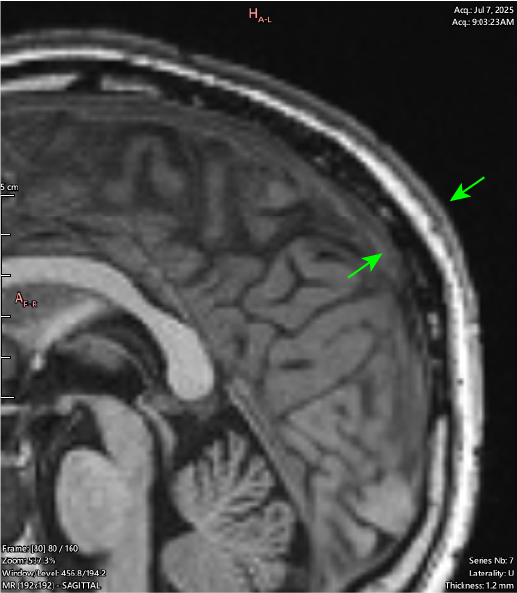

Corresponding MRI slices (JULY 2025):

JULY 2025:

VISIBLE SUNKEN DEFECTS ON SKULL(“SOFT SPOTS”):

T1 Sagittal

The same slice shown above (right), with a wider window setting to better demonstrate what is actively happening in this area.

There is hypointense soft tissue signal throughout the areas of skull destruction, including in the cortical layer of the skull (black signal out table of the bone). This demonstrates an active pathological process of osteolysis occurring, in which the bone is destroyed and replaced by this tissue.